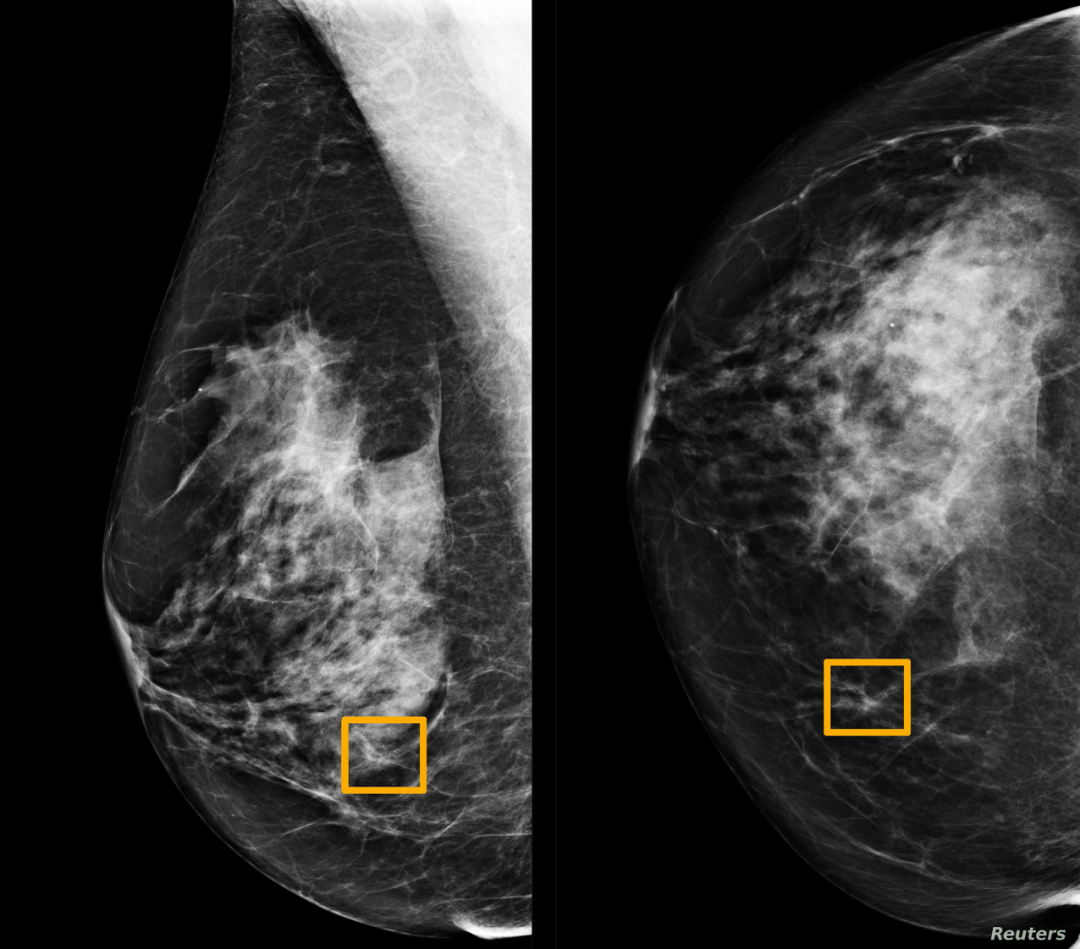

恶性预测 :该工具可预测乳房病变是恶性还是良性。对于患者病变的给定超声图像,提供病变的恶性诊断以及置信度(恶性概率)。

目前,研究团队已经发布了 web 应用程序,允许病人和医生使用该预测模型上传超声图像。用户可以上传一定数量的超声图像,然后根据需要选择超声筛查部分,在提交图像后,由模型计算预测结果,并用直方图显示模型图的置信度。